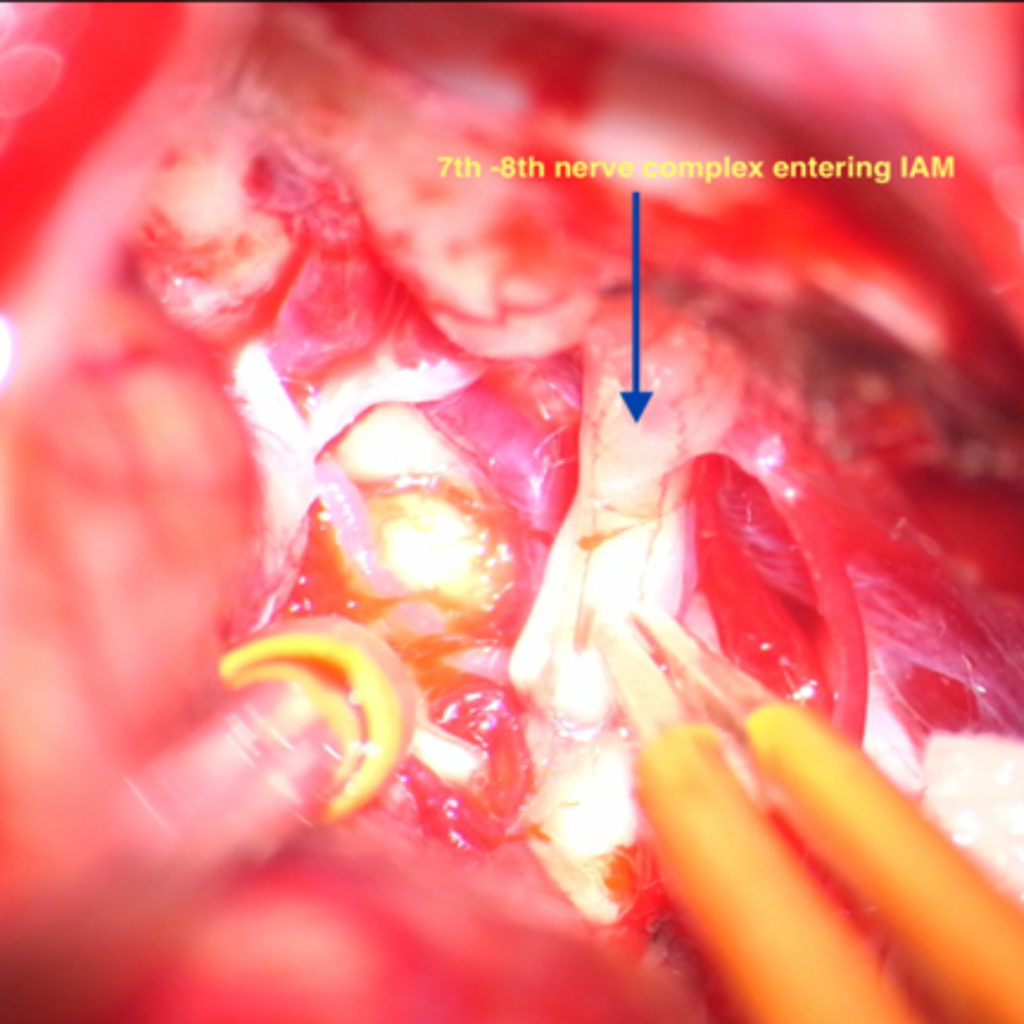

Facial -Vestibulocochlear nerve complex entering IAM